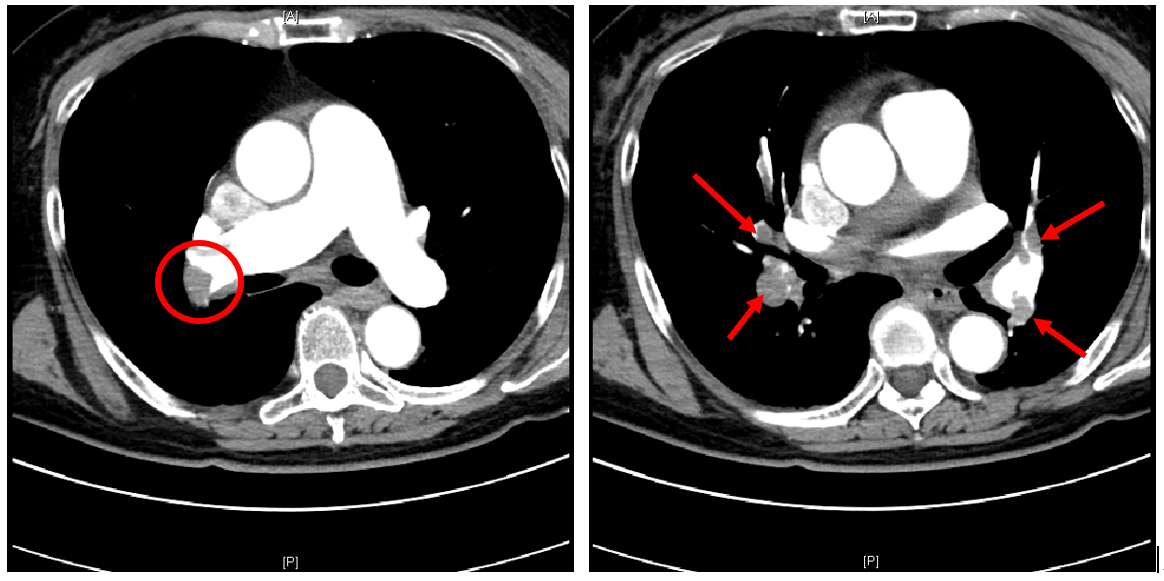

1 患者术前血管增强CT(红圈内或箭头所指为肺动脉内栓子)

在除外了急性心肌梗死之后,王女士的血管增强CT最终证实了大面积肺栓塞的诊断,此时的她需要依靠大剂量的血管活性药物维持血压,氧饱和度降至60-70%,血管外科医师紧急会诊后考虑大面积肺栓塞,目前病情危重,已经出现了休克症状,属于高危肺栓塞,随时可能面临生命危险,需要尽快进行手术治疗。